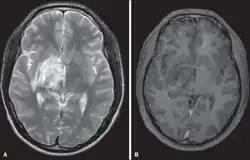

| Diagnostic method | Brain/Spine magnetic resonance imaging (MRI) [2] |

Diagnosis

Although there is a diagnostic criteria for Behçet's disease, one for neuro-Behçet's disease does not exist. Three diagnostic tools are mainly used.